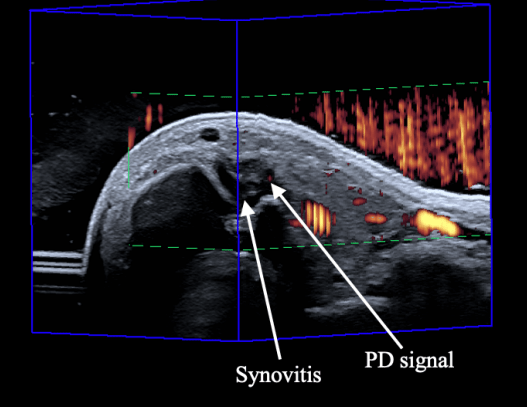

3D ultrasound to investigate synovial blood flow in 1st carpometacarpal osteoarthritis

This work demonstrates the ability of our 3DUS system to detect, quantify, and visualize vessel and synovial blood flow using Power Doppler and Superb Microvascular Imaging technology.